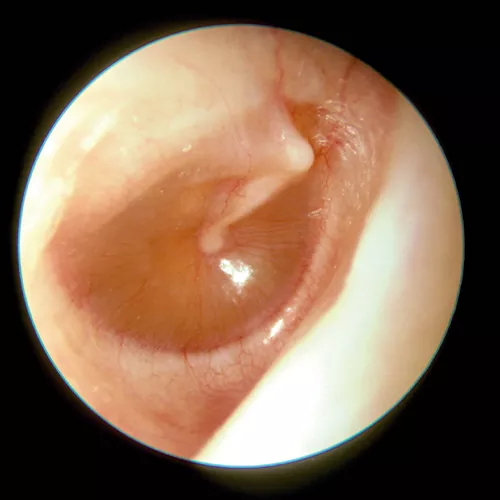

La otoscopia es la prueba fundamental para el diagnóstico, siendo definitiva en una parte importante de los casos. Existen muchas anomalías en la membrana timpánica asociadas a la otitis serosa. Por lo general, muestra un tímpano íntegro, edematizado y opaco con un aumento de la vascularización radial, y puede estar en posición normal, abombado o retraído. En los procesos de corta evolución la coloración suele ser rojiza, generalmente con una membrana engrosada. Sin embargo en los casos crónicos el aspecto suele ser azulado, resultado del depósito de hemosiderina en el exudado, y la membrana suele estar adelgazada y atrófica, con tendencia a la retracción, pudiendo desencadenar en una otitis adhesiva. En los casos en que el tímpano conserva su transparencia, es posible observar en ocasiones niveles o burbujas (indicativo de que la trompa funciona parcialmente).